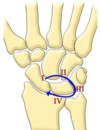

Diagnosis?

CIND

Radiocarpal instability

>50% ulnar translation of lunate on lunate facet